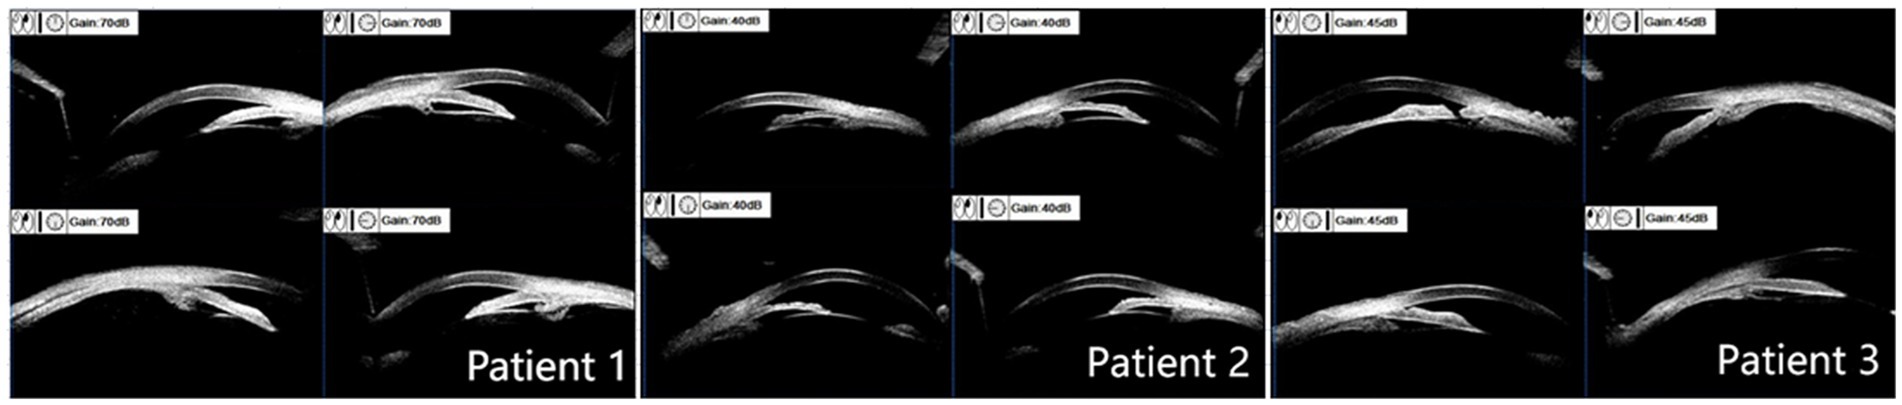

Ultrasound biomicroscopy

All three patients presented with iris bulging, anterior displacement of the ciliary body, and obstruction of the scleral spur at the iris root. The lens was in a normal position. For patients 1 and 2, one quadrant of the chamber angle was open with an extremely narrow gap, and the rest was all closed. For patient 3, complete angle closure was observed in all four quadrants, and the peripheral iridotomy incision was patent at the 1 o’clock position (Figure 2).

Figure 2

Ultrasound biomicroscope examination results. Patients 1 and 2: mild iris bulging, mild anterior displacement of the ciliary body, open temporal quadrant with an extremely narrow gap, all other quadrants closed, normal lens position. Patient 3: anterior displacement of the ciliary body in all four quadrants, scleral protrusion blocked by the iris root, chamber angle completely closed, patent peripheral iridotomy incision at the 1 o’clock position.